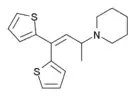

The pharmacodynamic response to an opioid depends upon the receptor to which it binds, its affinity for that receptor, and whether the opioid is an agonist or an antagonist. For example, the supraspinal analgesic properties of the opioid agonist morphine are mediated by activation of the μ1 receptor; respiratory depression and physical dependence by the μ2 receptor; and sedation and spinal analgesia by the κ receptor. Each group of opioid receptors elicits a distinct set of neurological responses, with the receptor subtypes (such as μ1 and μ2 for example) providing even more [measurably] specific responses. Unique to each opioid is its distinct binding affinity to the various classes of opioid receptors (e.g. the μ, κ, and δ opioid receptors are activated at different magnitudes according to the specific receptor binding affinities of the opioid). For example, the opiate alkaloid morphine exhibits high-affinity binding to the μ-opioid receptor, while ketazocine exhibits high affinity to ĸ receptors. It is this combinatorial mechanism that allows for such a wide class of opioids and molecular designs to exist, each with its own unique effect profile. Their individual molecular structure is also responsible for their different duration of action, whereby metabolic breakdown (such as N-dealkylation) is responsible for opioid metabolism.

There are a number of broad classes of opioids:[260]

- Fully synthetic opioids: such as fentanyl, pethidine, levorphanol, methadone, tramadol, tapentadol, and dextropropoxyphene;